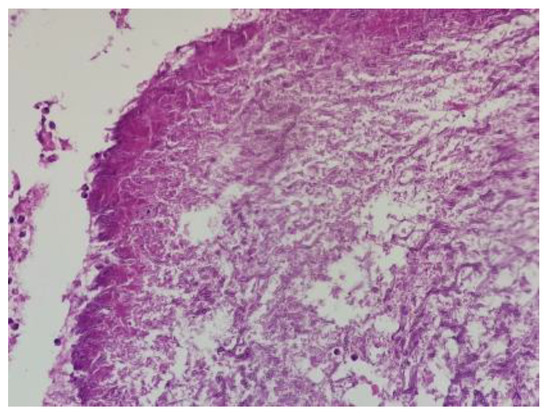

2.5. Pathology Report